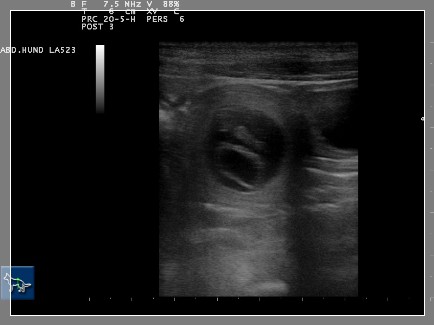

Die ersten Ultraschallbilder aus der Tierarztpraxis